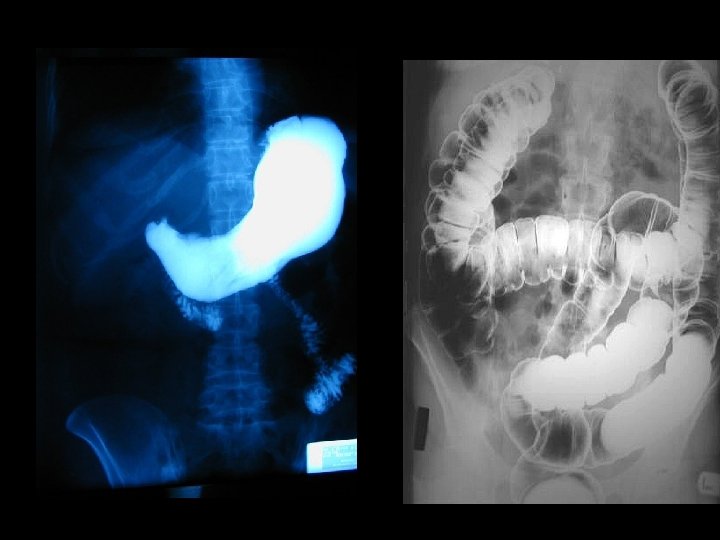

FLUOROSCOPY IMAGES IN MOTION